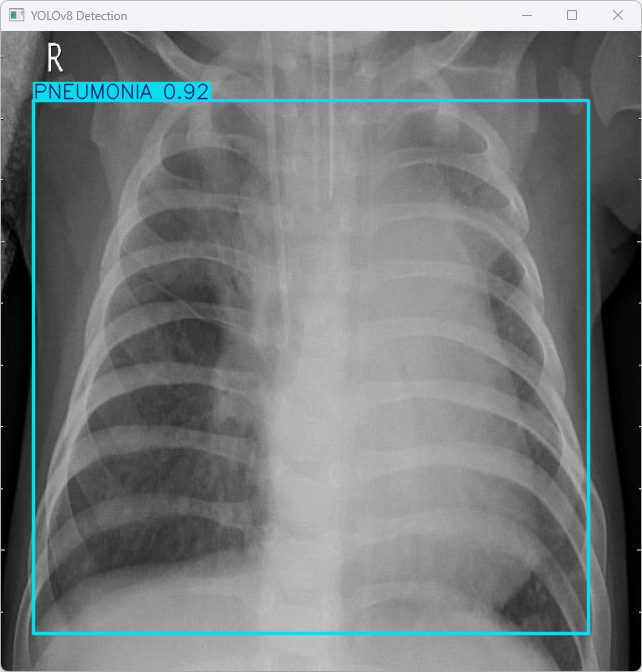

执行imgTest.py代码后,会将执行的结果直接标注在图片上,结果如下:

这段输出是基于YOLOv8模型对图片“imagetest.jpg”进行检测的结果,具体内容如下:

图像信息:

(1)处理的图像路径为:TestFiles/imagetest.jpg。

(2)图像尺寸为640×640像素。

检测结果:

(1)检测到 1 个 PNEUMONIA(检测出图像中含有肺炎特征)。

处理速度:

(1)预处理时间: 7.0 毫秒

(2)推理时间: 5.0 毫秒

(3)后处理时间: 86.0 毫秒

总结:

模型成功检测出图像中的肺炎特征,并以高效速度完成了预处理、推理和后处理,表明系统具备快速响应的能力,适合实际应用场景。